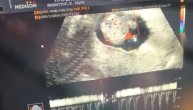

Veljko snimio prve otkucaje srca Željka Ražnatovića